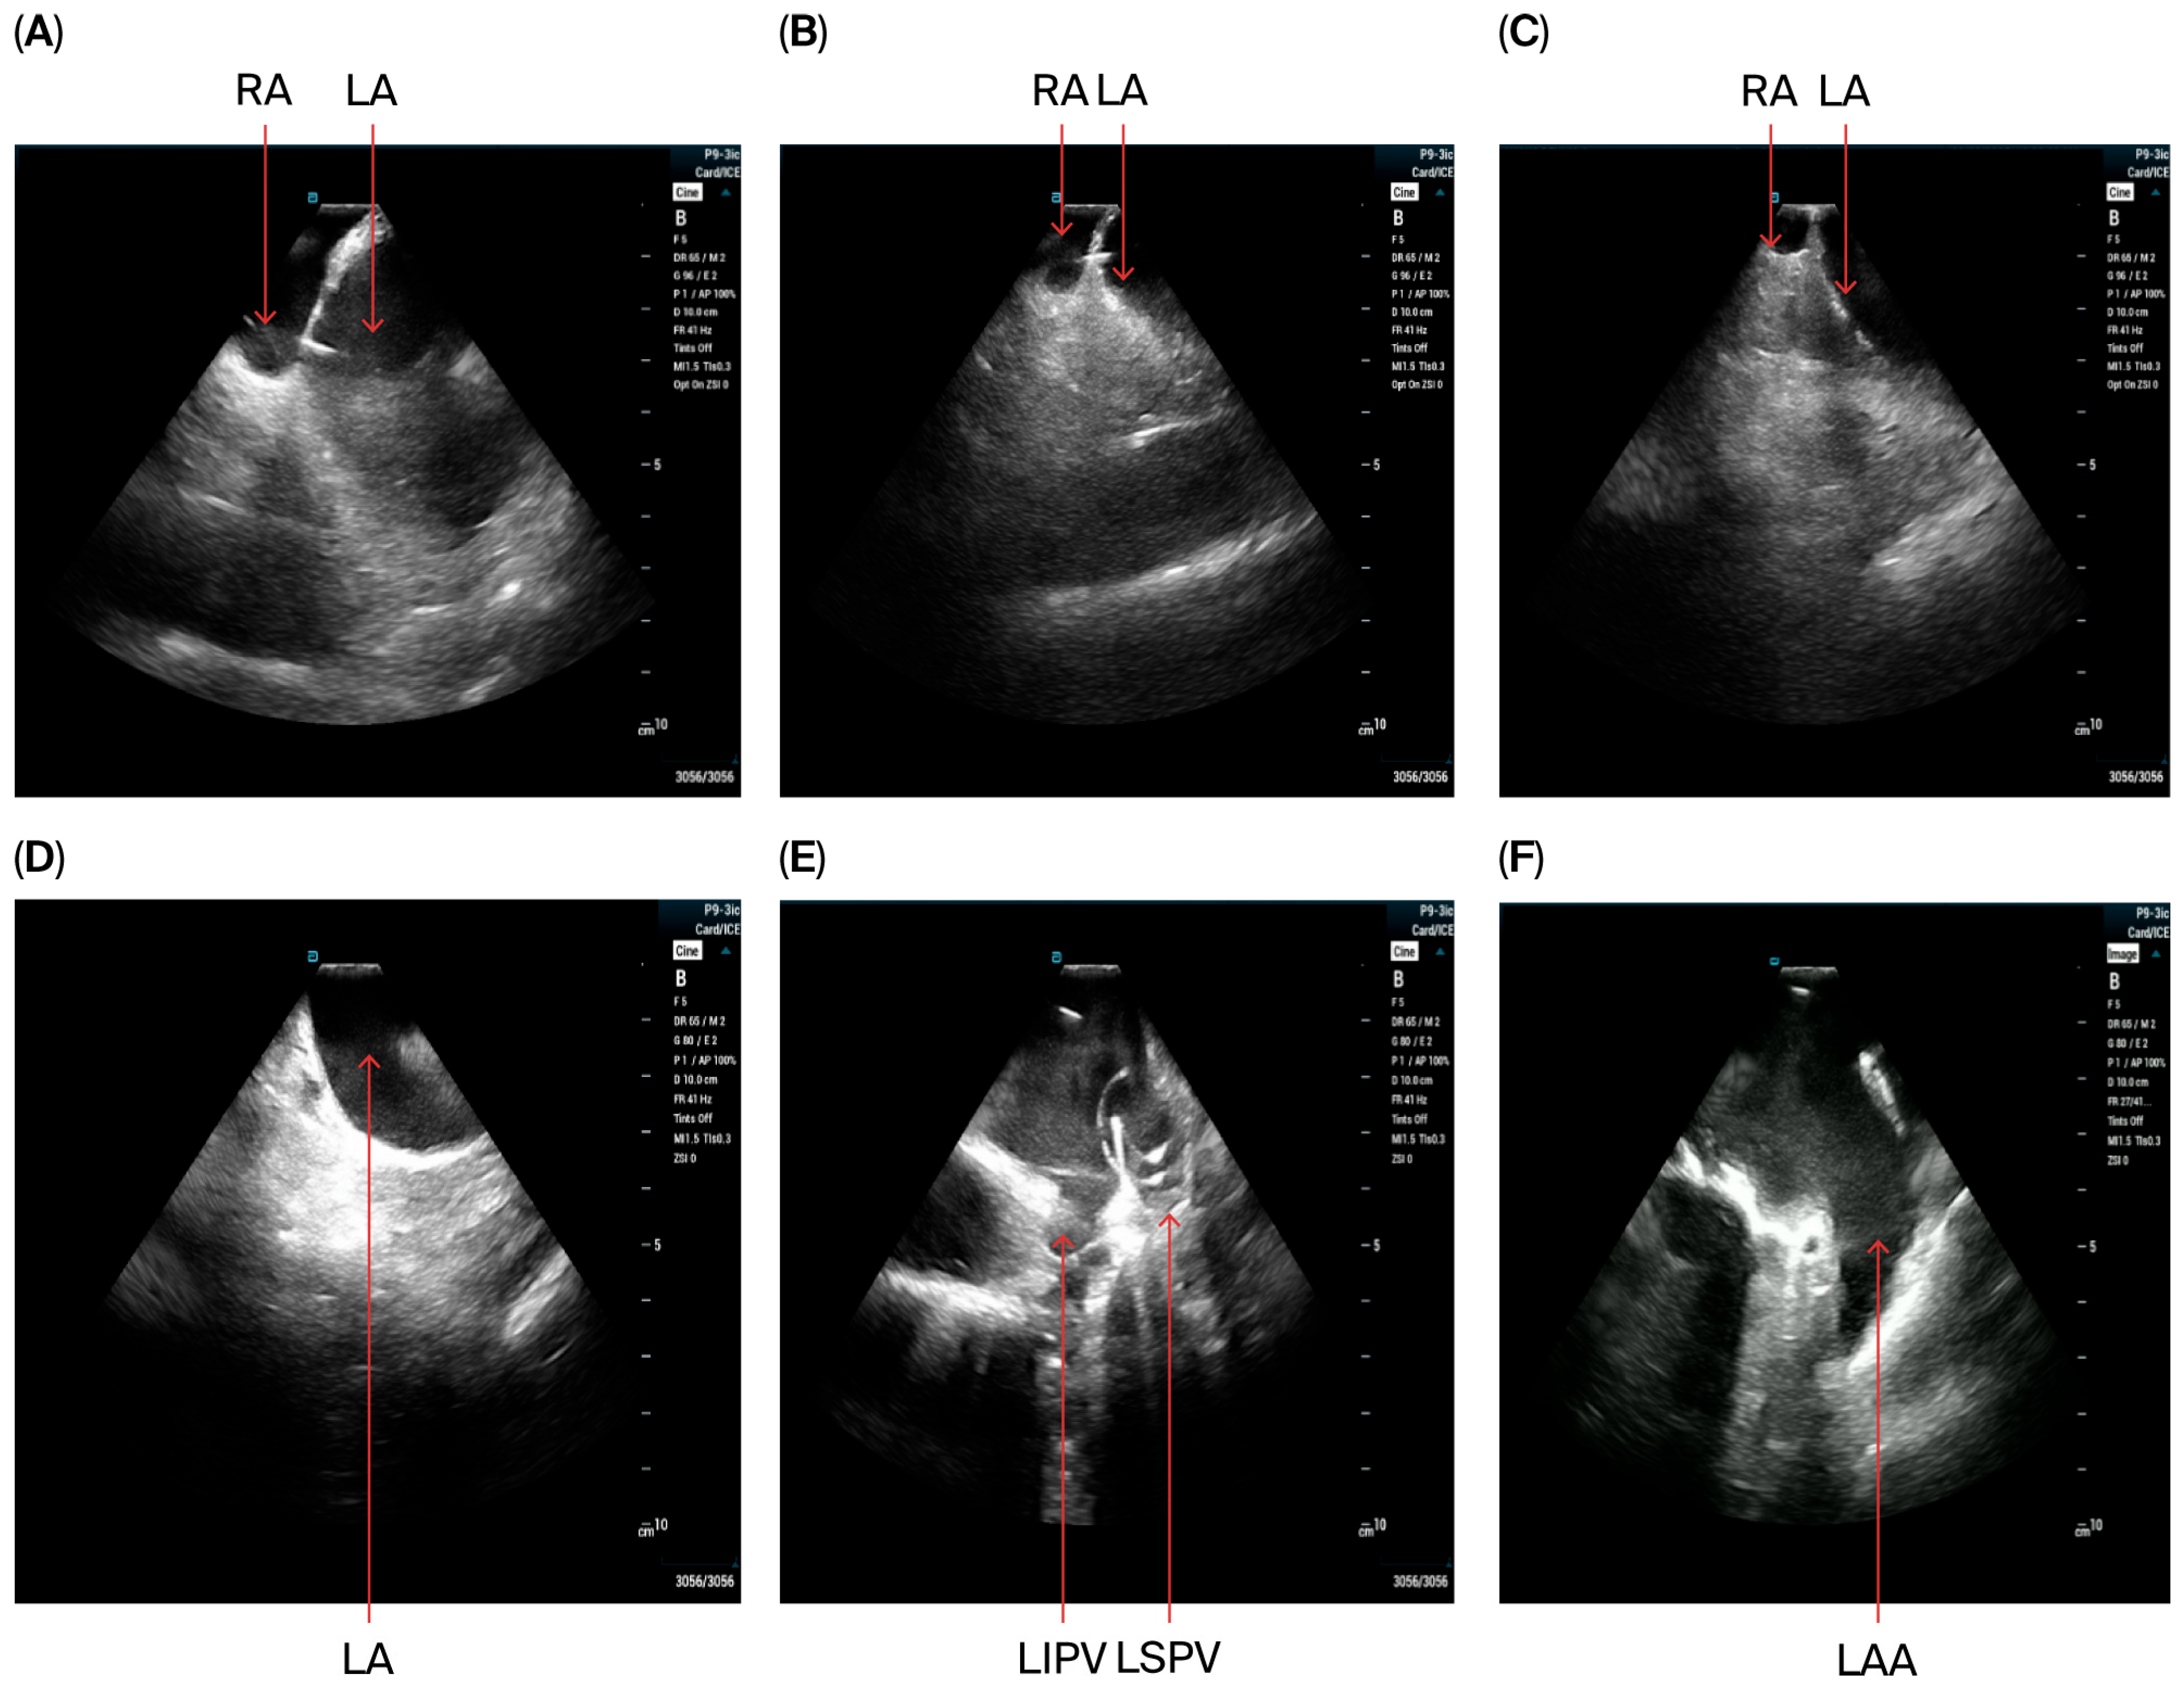

- The VersaCross sheath was exchanged for the Faradrive sheath and dilatator. After predilatation of transseptal puncture, the Faradrive sheath was retracted, and the ICE catheter was advanced along the VersaCross wire to the left atrium (Figure 1A–D). Then, the Faradrive sheath was moved back to the LA, and the dilator and Versacross wire were removed, with the ICE catheter and PFA sheath placed in the LA via a single transseptal puncture.

- ICE images of the LA, including the LAA, were obtained from all patients to exclude LAA thrombus (Figure 1E).

- A circular mapping catheter (CMC) or high-density catheter (with repeated ablation) was advanced to the LA via the Faradrive sheath. Electroanatomic mapping of the LA, including detailed voltage assessment was performed. Then, over the J-tip wire, the Farawave pentaspline catheter was advanced to the LA via the Faradrive sheath. The 0.035-inch J-tip guidewire was attached to the EnSite mapping system’s pin box via a DuoMode extension cable (Boston Scientific, Marlborough, MA, USA) for additional visualization in LA and pulmonary veins. ICE catheter imaging was used to ensure appropriate catheter positioning and catheter–tissue contact with each PV and LAPW PFA lesion delivered. Prior to ablation, 0.2 mg of intravenous glycopyrrolate was administered to all patients to avoid vagal reactions during PVI.

- PV isolation was performed with the PFA catheter placed at the PV ostium, with 4 applications in the basket configuration and 4 in the flower configuration for a total of 8 applications per PV. Appropriate rotation of the catheter following 2 applications in each position was assured with LA ICE and EAM visualization. Two additional applications in the flower configuration were delivered at the operator’s discretion in the left and right carina, towards the LA ridge and septal aspect of the right pulmonary veins based on the anatomy and presence of atrial potentials.